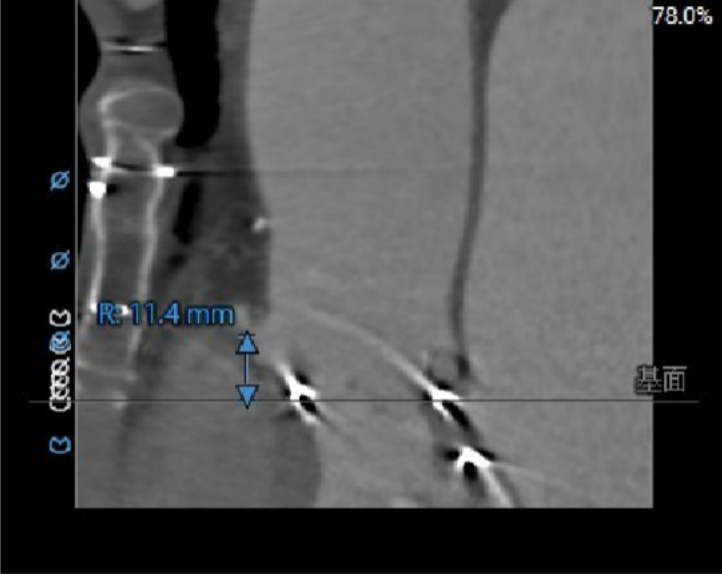

冠脉风险:LCA:8.0mm,RCA:11.4mm;外科瓣术后,SOV:34.0*36.3*36.4mm,STJ:33.8mm,冠脉堵塞风险低;